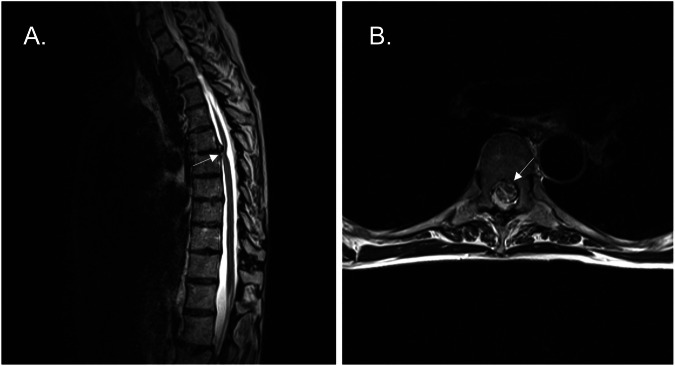

Methods: This case series study is based on routinely collected data. Forty-eight (48) cases were identified as having an ISCH on MR imaging, between 2009 and 2019. Their medical files have been searched retrospectively. Patient characteristics were described according to their asymptomatic or symptomatic status.

Results: The mean age of patients at the time of diagnosis was 52.5 years. Most of the patients identified were asymptomatic (69%) and followed clinically. The main neurologic presentation for the symptomatic group was Brown-Séquard-like syndrome. 20% of the symptomatic patients were rapidly treated surgically after consultation with the neurosurgeon. The mean follow-up duration was 56 months for asymptomatic patients and 51 months for symptomatic patients. Most of our patients (41 out of 45) were considered stable or unchanged at follow-up. There was no neurological progression in all asymptomatic patients.